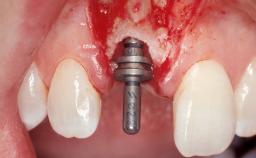

Type of Implants One-Piece

Attachment One-Piece

Placement Protocol Early or late implant placement

Bone Volume Deficient horizontally, requiring prior grafting